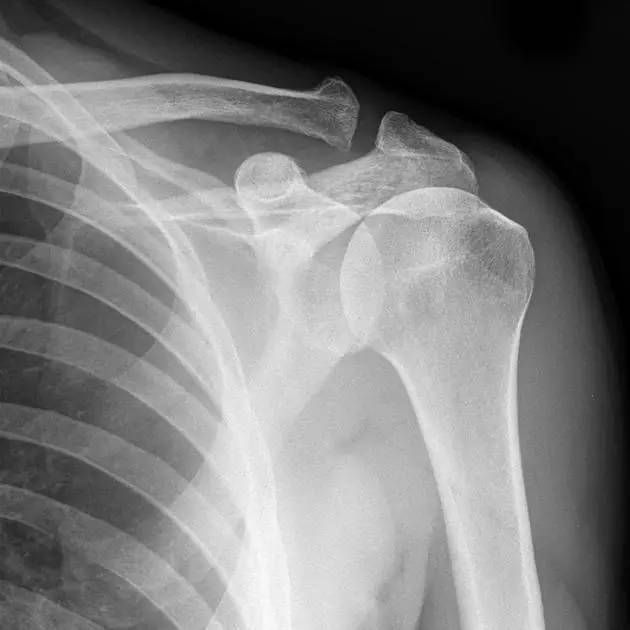

正常肩关节(来源:Radiopaedia)